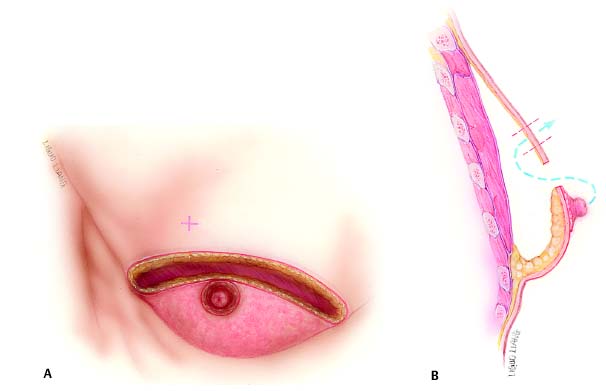

Surgical management of male chest deformities has evolved to treat all degrees of the condition. The least invasive procedure, liposuction, which is advocated by many authors,4–6 produces excellent results. Rohrich et al2 advocate ultrasonic liposuction as a more efficacious modality for contour correction. It is uncommon that postbariatric patients are candidates for liposuction alone because the redundant skin cannot be addressed. Prior to the availability of liposuction, an open surgical approach was the only option. In 1946, Webster7 described a corrective procedure that employs a semicircular incision within the pigmented areola through which glandular resection is performed. His discussion does not mention problems with redundant skin, even in the large reductions, and he emphasizes the importance of keeping the scar within the areola. Letterman and Schurter8 describe a technique utilizing nipple transposition via an oblique approach initially developed by Dufourmentel and Mouly9 for breast reduction and mastopexy. Here a pedicle bearing the nipple–areola can be moved to the desired position on the chest wall. Pitanguy10 utilizes a transareolar incision for open management. Davidson11 employs a concentric circle method to resect redundant skin, with open resection of excess breast tissue and fat. An oval design is used when nipple elevation is necessary, carrying the nipple–areola on a dermal pedicle. A case report by Silfen et al12 describes an inferiorly based dermal flap to augment the breast and allow nipple–areola transposition. The transposed flap provides volume repletion to the pectoral region. The result illustrated exhibits incorrect nipple position and scars in a nonanatomic position, not in the inframammary fold. Hammond13 utilizes a circumvertical technique when skin excision is necessary. Here a medial inframammary scar is avoided, and the vertical component of the incision reduces periareolar tension seen in the concentric circle technique to achieve less scar hypertrophy and widening. Gusenoff et al14 define pseudogynecomastia as increased amounts of subareolar fat without enlargement of the glandular component of the breast. Many massive weight loss (MWL) patients fit into this category with the additional component of excess skin. The technique utilized in grade 2 gynecomastia by these authors is a thin inferiorly based dermal pedicle, which can be modified to correct the lateral chest and breast deformities. They advocate a free nipple graft procedure for grade 3 gynecomastia. More severe deformities require skin excision in addition to glandular resection.

Patients with large breasts and MWL patients have in common a large amount of excess skin that cannot be managed in one stage without an incision beyond the areola. Additionally, the pedicled procedures preserve subareolar volume to achieve appropriate contour. The procedure described in this chapter employs an inferior pedicle similar to the reliable one utilized widely in female reduction mammoplasty. Subcutaneous mastectomy is accomplished to remove excess tissue, preserving the upper flap, which is advanced over the pedicle to the inframammary fold. An opening is cut in the flap to admit the nipple–areola. In addition to providing blood supply to the nipple–areola, the pedicle favorably augments the contour above the inframam-mary fold. MWL patients often display large skin excess that extends laterally to the axilla and arm. The lateral inframam-mary incision can be extended posteriorly to provide skin excision and contour correction in these areas.